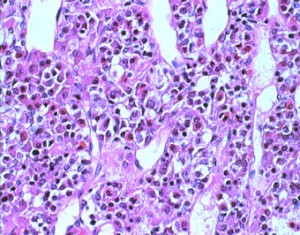

下垂体からはさまざまなホルモンが分泌されますが,プロラクチンを作る細胞は多くて,副腎皮質刺激ホルモンを作る細胞は少ないです。細胞の大きさと分布にも特徴があります。下にある病理画像はそれぞれのホルモンを特殊な染色法で染めたものです。細胞の中のホルモンの分子が染まっています。

正常下垂体の細胞とホルモン(ホルモン免疫染色)

左がHE染色といいます。右の写真はプロラクチン PRL 産生細胞を免疫組織染色で染めたものです。

左は成長ホルモン GH ,右は副腎皮質刺激ホルモン ACTH を産生する細胞です。

左は黄体化ホルモン LH,右は卵胞刺激ホルモン FSH産生細胞です。

甲状腺刺激ホルモン FSHです。